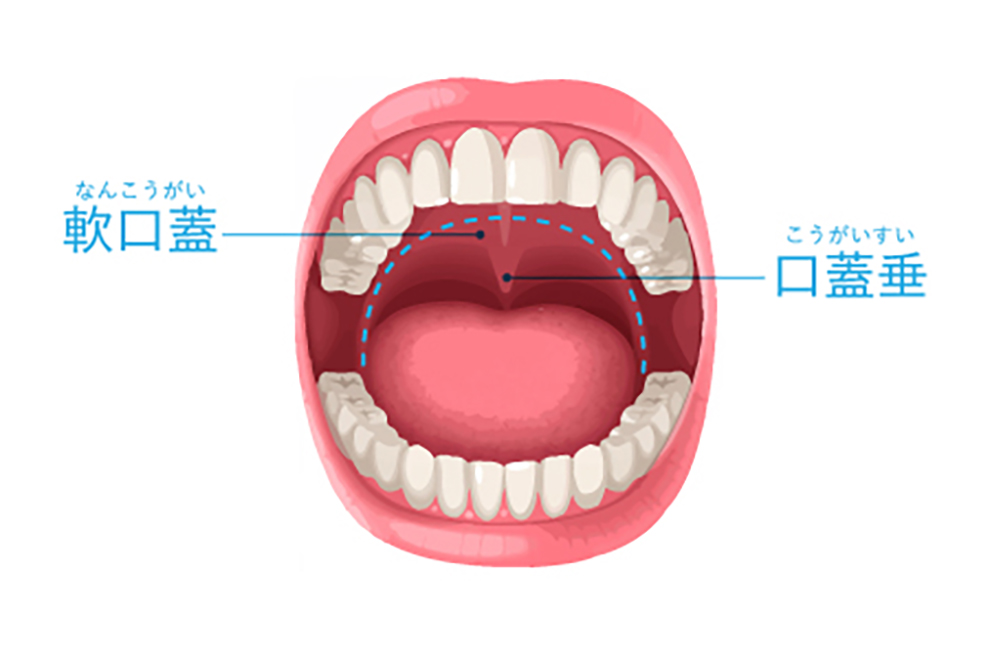

仰向けで寝ると、重力によって舌根(舌の付け根)や軟口蓋(喉の奥の柔らかい部分)が沈み込み、気道を狭くしてしまいます。

狭くなった気道を空気が通る時に、粘膜が振動して出る音が「いびき」です。

そして、気道が完全に塞がれてしまうと「無呼吸」になります。

これまでのいびき治療における外科手術は、メスで口蓋垂(のどちんこ)や軟口蓋を切り取るものであり、術後の激しい痛みや出血、食事の制限などが伴いました。

Er:YAG(エルビウムヤグ)レーザーという特殊なレーザーを、喉の奥の粘膜(軟口蓋や口蓋垂)に照射します。

レーザーの穏やかな熱作用によって、緩んだ粘膜組織を引き締めると同時にコラーゲンの再生を促進します。

たるんでいた粘膜がキュッと引き締まり、持ち上がることで空気の通り道(気道)が広がり、いびきや無呼吸が改善されます。